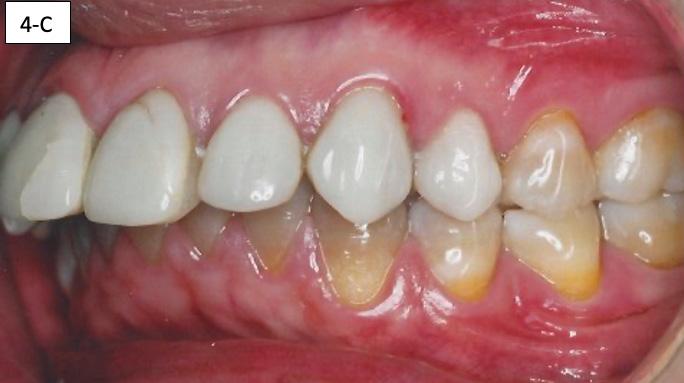

FIG. 4C: Pre-treatment, left lateral view

Clinical dental appraisal revealed full Angle Class II molar and cuspid relationship. The arches were wide and there was a moderate crowding. The patient had 9.0 mm overjet and 6.0 mm overbite. However, the patient reported SDB symptoms, and he also presented with symptoms and signs of TM dysfunction (Figure 4A, B, C, D, E, F))

Clinical Micro-esthetic appraisal revealed signs of attrition and abrasion. Periodontal health was good, and the patient was devoid of tooth decay. However, there was a moderate number of restorations, generalized Tetracycline stain and failing porcelain veneers on the maxillary anterior teeth.